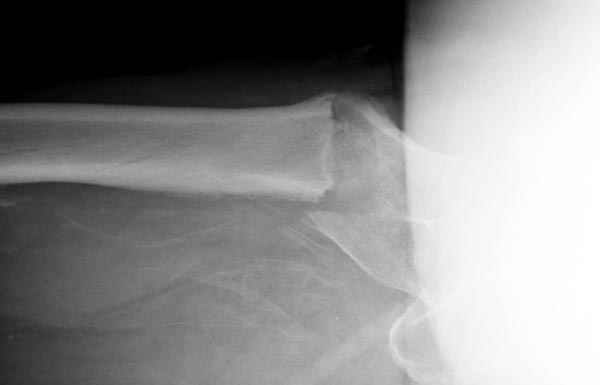

Здесь сканнированные снимки импланта и операционные снимки больной.

Уважаемые коллеги, Александр Николаевич!!! Очень достойный выход из сложнейшей ситуации. У нас лежит похожий пациент. Хотелось бы обсудить вот какой ворос. Почти все ятрогенные переломы шейки бедра при антеградной штифтовании - вертикальные. Понятно, что при многоуровневых переломых не до жиру. Но все же, как фиксировать вертикальный перелом шейки? Только отрепонировав или вальгировать проксимальный отдел бедра(если есть такая техническая возможность)???